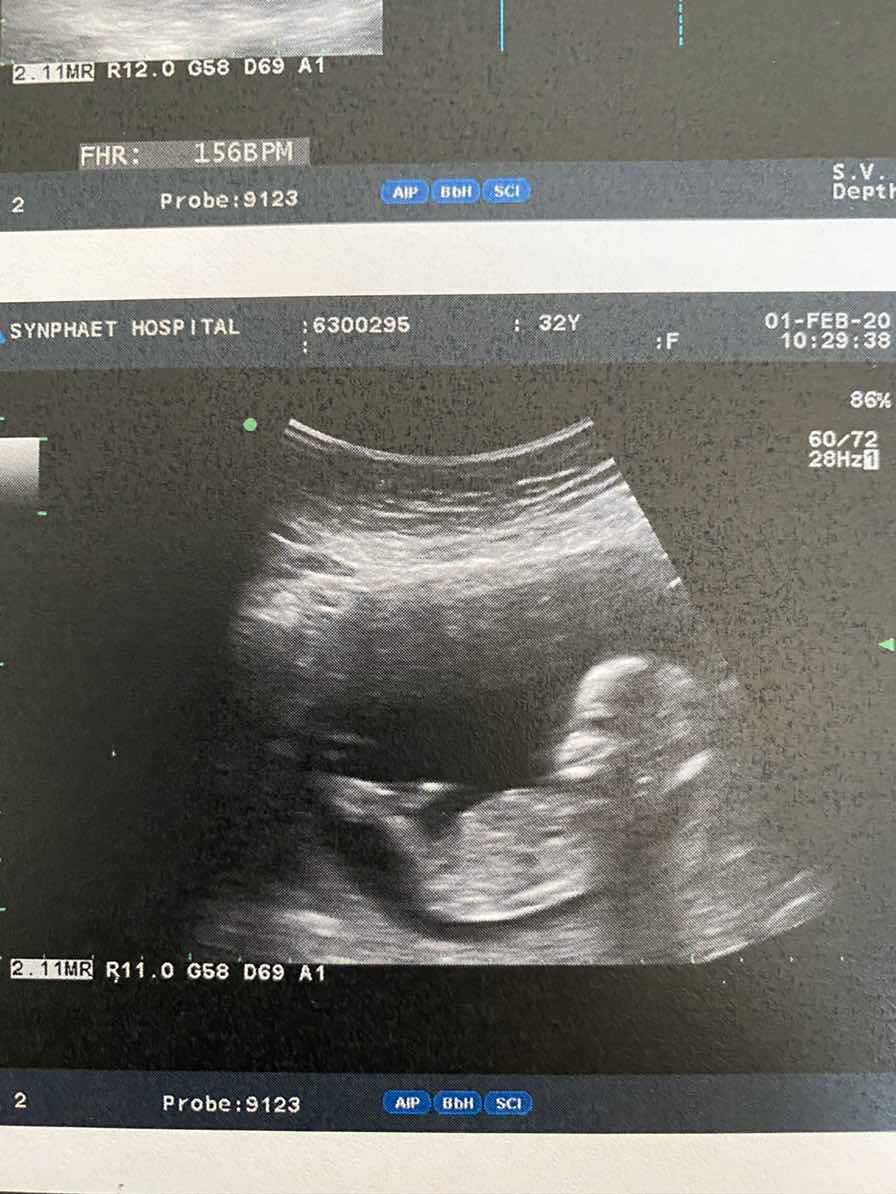

รูปแรกค่ะ ไปซาววันนี้ 14วีค ขอดูรูปแม่แม่ ตอนซาวประมาณ12-15วีค หน่อยนะคะ

14วีค4วัน